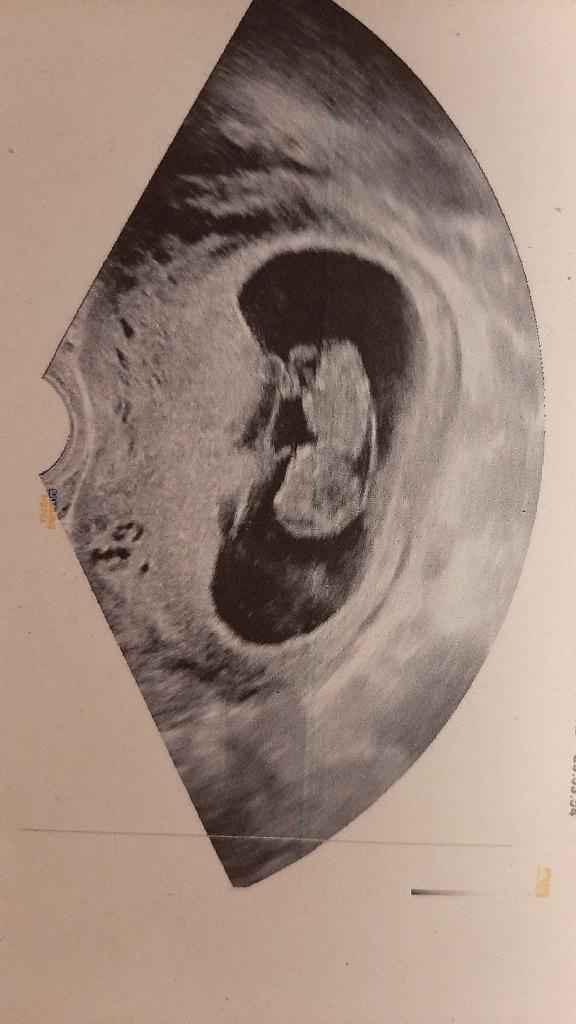

Ciao ragazze😀😀 Oggi a 7+4 ho fatto la mia prima ecografia. Secondo voi, secondo il metodo Ramzi, è maschio o femmina?

Ciaooooo, 7+4,secondo voi è maschio o femmina???

• Rispondi

Ciaooooo eco 3d a 7+5....secondo te lulu è maschio o femmina?